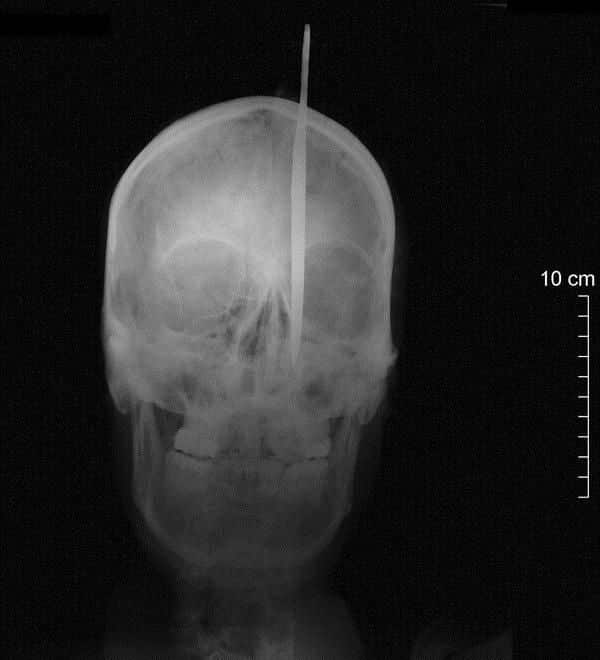

gif_animation 幻覚や幻聴、妄想や心神喪失など、様々な症状をもたらす脳の病気(精神病)「統合失調症」。その重度患者が行ったという常軌を逸した自殺。自らの頭部を、ナイフで何度も刺した…。実際の画像だけでなく、レントゲン写真も凄まじい。[4]images